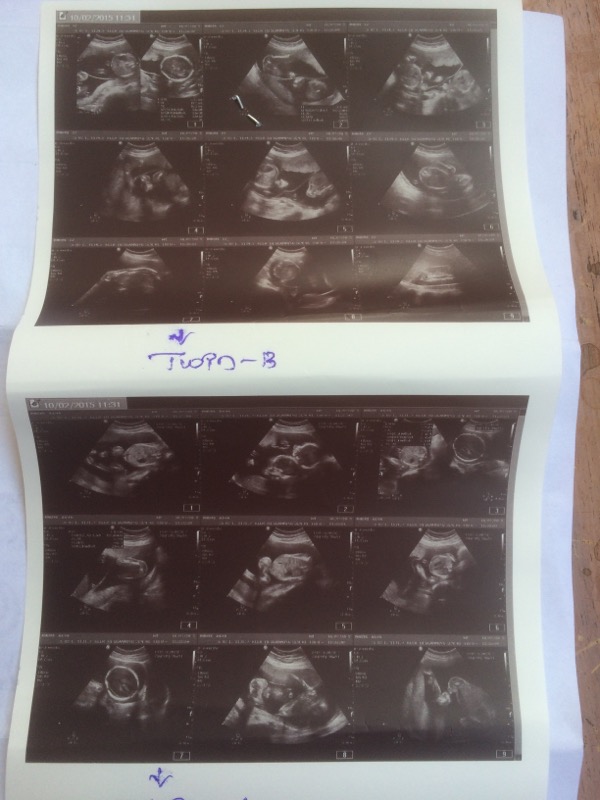

Attachment 23643 Hi All, can anyone please confirm by looking into the ultrasound pics either both are boys or girls or a boy and girl :)

Not super sure, but Twin B boy and Twin A girl, maybe? Twin A has a potty shot but it doesn't show much, twin B maybe has a potty shot?

Twin A is boy and twin B is a girl as per what has been informed to me.. But I am not too sure too....

I thought two boys.